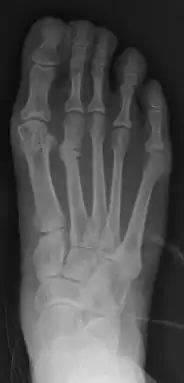

For recurrence correction after fusion procedure (Fig. 9) Metatarsus primus varus deformity and pain recurred 6 months after modified Lapidus procedure and it could also be again corrected by the syndesmosis procedure.